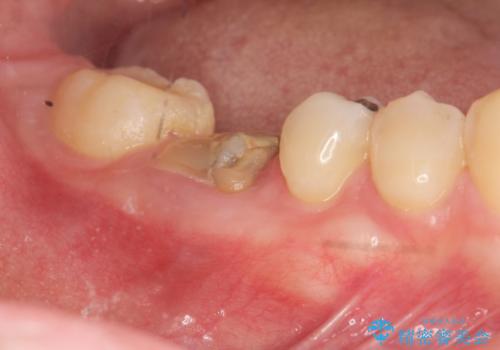

[ 歯周外科 ] 縁下マージン・縁下カリエスの治療

![[ 歯周外科 ] 縁下マージン・縁下カリエスの治療の症例 治療前](https://seimitsushinbi.jp/wp/wp-content/uploads/2022/04/b464b4c5c3053a5fc84212fb664a039f-500x350.jpg?v=1648866777)

![[ 歯周外科 ] 縁下マージン・縁下カリエスの治療の症例 治療後](https://seimitsushinbi.jp/wp/wp-content/uploads/2022/04/bd017e5dbd742f9bb33f09d39c8f1b52-500x350.jpg?v=1648866850)